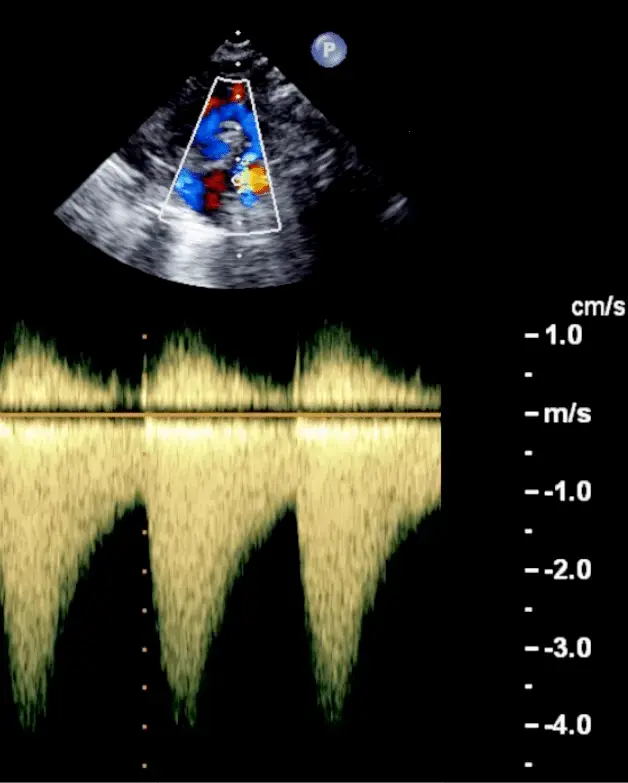

- Aortic velocity is measured using continuous-wave doppler ultrasound with examination from multiple acoustic windows

- Mean gradient is calculated by averaging instantaneous gradients over the systolic ejection period using the modified Bernoulli equation,

- Use if mean gradient < 40 mmHg or peak velocity < 4 m/s

| Peak velocity (m/s) | <2.0 m/s | 2.0-2.9 | 3.0-3.9 | ≥4.0 | ≥5.0 |

Underestimation due to improper Doppler alignment across the Aortic Valve

If not parallel to the AS jet, you will not get the highest mean AV gradient or peak velocity across the AV → underestimate severity of AS. Importantly, you cannot overestimate the gradient (Exceptions: significant anemia or Subaortic Stenosis).

- The above figure is from the Mayo Echo Boards video where the presenter highlights the importance of calculating the AV TVI in multiple windows to ensure you are appropriately calculating the highest VTI and avoid miscalculation/miscalssification. In Thaden et al (JASE, 2015), the authors found that peak velocity was found outside of the apical window 61% of the time and that neglecting non-apical window misclassified AS 23% of the time.

- ⚠️ Elderly patients may have vascular stenosis → elevated AV VTI measurement outside of the apex.